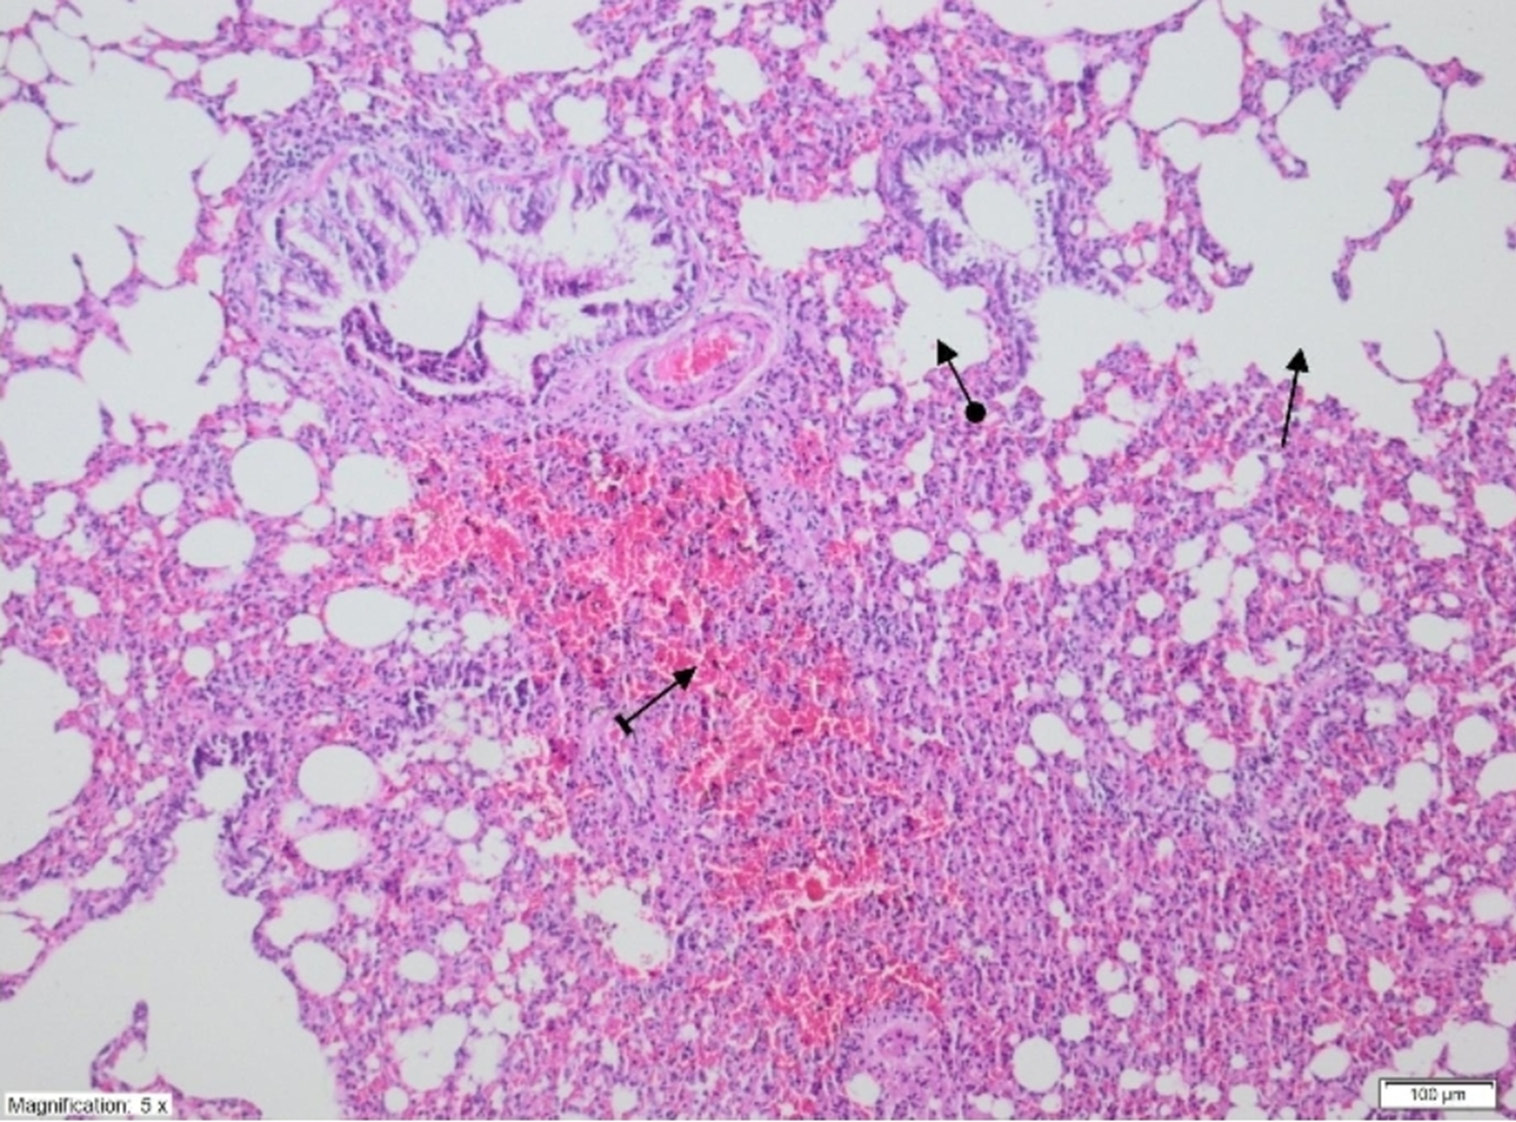

On histopathological examination, the alveolar vein, bronchiole structures and pleural mesothelium were identified as normal in pulmonary tissues in the SG group (Figure 4). However, significant areas of alveolar degeneration, edema and hemorrhage were observed in the pulmonary tissues of the LIR group (Figure 5). Congestion, PMNL and lymphocytic infiltration were observed in the lung tissues in the LIR group (Figure 6). In the lung tissue of the RLIR group, the pleural mesothelium, and alveolar, vascular and bronchial structures were identified as normal, which was similar to the observations in the SG group (Figure 7).